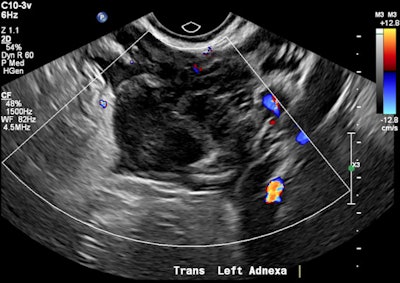

A 32-year-old female presented with severe constant left lower abdominal pain, per vaginal spotting and nausea. A pelvic ultrasound performed at six weeks' gestation demonstrated a viable intrauterine gestation and a small perigestational hematoma. A heterogeneous mass was noted abutting the left ovary. It featured peripheral vascularity, but no internal vascularity. There was small-volume pelvic free fluid with low-level internal echoes consistent with hemoperitoneum (see three images below).

Transvaginal ultrasound in transverse orientation. The left adnexal mass demonstrates a hyperechoic tubal ring sign (blue arrows). The uterus (red arrows) demonstrates a double decidual reaction.The patient decided to have an outpatient surgical termination of the intrauterine pregnancy. A follow-up ultrasound was performed two days post termination due to increasing abdominal pain. A round, thick-walled avascular structure with a central hypoechoic component was seen within the left adnexa. It featured a hyperechoic rim consistent with a tubal ring sign. However, the left ovary was not identified. A moderate volume hemoperitoneum was also seen.